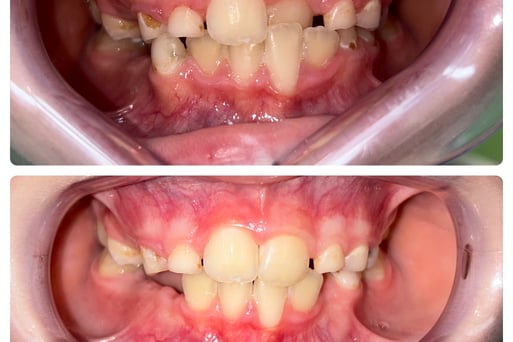

Aparatele dentare mobile sunt utilizate in tratamentul anomaliilor dento-maxilare, forme usoare sau moderate. Se numesc mobile pentru ca sunt purtate doar pe timpul noptii, plus cateva ore ziua.

Varsta ideala pentru inceperea tratamentului este la 6-7 ani ( dentitia mixta),copiii fiind in crestere, iar maxilarele destul de maleabile pentru a raspunde bine la tratament.

Cu ajutorul acestora putem corecta pozitia dintilor, muscatura, largi arcadele, imbunatatind aspectul zambetului si functia.